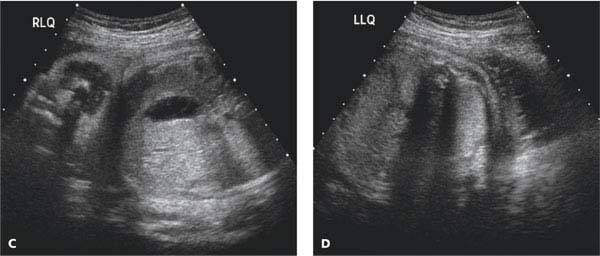

The AFV undergoes characteristic changes with gestation. Pharmaceutical drugs are sometimes prescribed to treat polyhydramnios, such as indomethacin, but concerns have been raised over implications to the unborn baby and other side-effects.Physiology Change in volume through gestation If a fetal bladder obstruction is the cause of oligohydramnios, a small tube can be placed in the bladder to allow the fluid to flow into the amniotic sac. If the cause of the condition is known, then other treatmentsmay be applied. If needed, this option can be done more than once. The opposite is done in treatment of polyhydramnios, where a syringe is inserted into the amniotic sac to drain excess fluid. In some cases of oligohydramnios, extra fluid has been added to the mother's amniotic sac in an effort to increase amniotic fluid levels within the uterus. The amniotic fluid index chart shows the average volume of amniotic fluid in a pregnant woman based on gestational agein millimeter. There areseveral approachesto test the most commonly used methods are the four-quadrant techniqueand the 'single deepest pocket'. Unfortunately, effective treatments for polyhydramnios and oligohydramnios are limited. The amniotic fluid index (or AFI) is used to estimate the well-being of the fetus by doing an ultrasound of the uterus to estimate the levels of amniotic fluid levels in the uterus. Possible Treatments for Polyhydramnios and Oligohydramnios Polyhydramnios can also lead to certain congenital complications, including Down’s syndrome. Polyhydramnios can lead to many of the same complications as oligohydramnios, and the extra fluid can leak through the vagina in rare instances. The symptoms of polyhydramnios for this include edema, difficulty breathing, and excessive weight gain. There are often no symptoms experienced by the mother, except for their belly not growing in alignment with their duration of pregnancy, being smaller than it should. Having low levels of amniotic fluid inside the uterus during pregnancy can lead to numerous problems, which include miscarriage, premature birth, and stillbirth. With the amniotic fluid index chart above, you will wander what are the possible complications along with oligohydramnios and polyhydramnios? Low Amniotic Fluid Levels If there are high amounts of amniotic levels in a mother's uterus then it is known as polyhydramnios, whereas having small amounts of amniotic fluid can lead to oligohydramnios. What If I Have Abnormal Amniotic Fluid Levels? With the pregnancy process going on, the AFI values are changing, and the percentile for fetus age is usually referred as the cutoff value. The AFI 250mm is assumed as polyhydramnios. After 35 week, AFI levels usually begin to reduce. An average AFI level is 80 mm to 140 mm when you are in your 20 weeks to 35 weeks of pregnancy. Usually, the normal value of amniotic fluid index varies from 50 mm to 250 mm (or 5 cm to 25 cm). The sum of the four quadrants, in millimeters or centimeters, is amniotic fluid index. The deepest pocket without fetal parts or umbilical cord is then measured in millimeters or centimeters vertically. Using the umbilicus and the linea nigra as horizontal and vertical axis, an imaginary divide is created inside the uterus, which is split into four quadrants. Techniques and Values of Amniotic Fluid Index Charts Technique The amniotic fluid index chart shows the average volume of amniotic fluid in a pregnant woman based on gestational agein millimeter.Īmniotic Fluid Index Chart Percentile Values

The amniotic fluid index (or AFI) is used to estimate the well-being of the fetus by doing an ultrasound of the uterus to estimate the levels of amniotic fluid levels in the uterus. Assessing amniotic fluid determines an important dimension of fetal health.